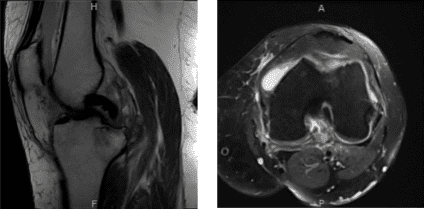

An MRI result was presented during her follow-up visit and it showed Osteoarthrosis with high-grade cartilage loss in the medial compartment and high-grade cartilage loss central trochlear cartilage with low-grade chondral loss patellar cartilage.

Subchondral cystic changes and edema in the medial tibia are seen. This may be secondary to osteoarthritis although I cannot exclude developing insufficiency fracture medial tibia.

Large radial tear posterior horn medial meniscus which is peripherally extruded. Pes anserine bursitis. Large knee joint effusion with loose intra-articular body.

MRI-Left Knee Non-contrast